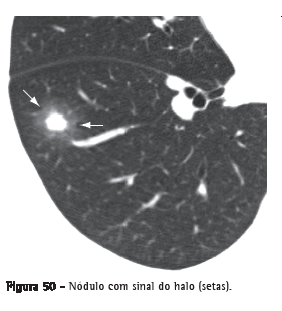

Sinal do halo

Opacidade em vidro fosco que circunda um nódulo, massa ou uma área de consolidação arredondada (Figura 50). Foi inicialmente descrito como um sinal de hemorragia ao redor de um foco de aspergilose angioinvasiva,(82) sendo bastante específico no contexto de paciente neutropênico febril, surgindo precocemente.(82) O sinal do halo pode ser causado por hemorragia associada a outros tipos de doença (por ex. candidíase, sarcoma de Kaposi) ou por infiltração pulmonar local por neoplasia.(83-86)